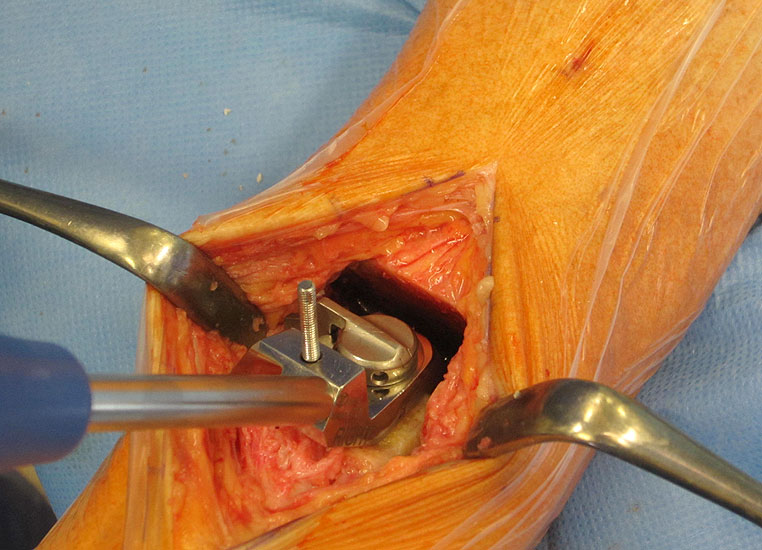

• Gefahren

1. Wundheilungsstörung infolge einer hohen intraoperativen Druck- und Zugbelastung auf den periartikulären Weichteile; Lösung: dosierte Weichteilbehandlung durch die Hacken durch den Assistenten; aktive Erinnerungen während der Operation (Abb. 20 und 21)